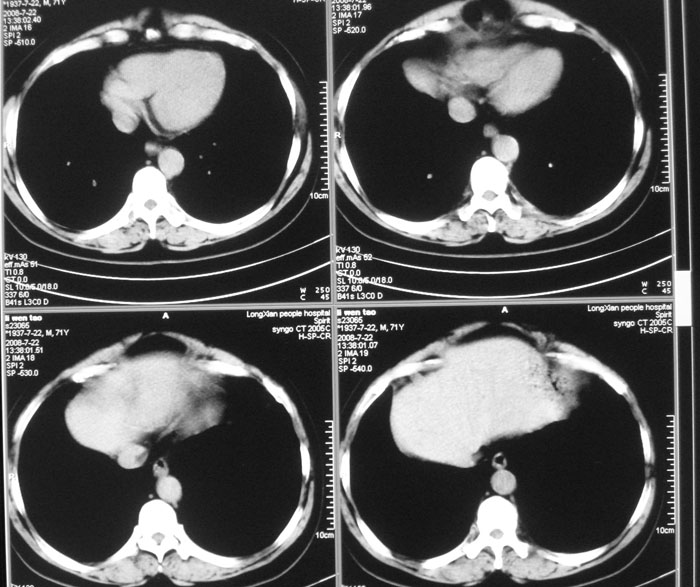

以下是引用zhangjixiang在2008-8-6 20:02:00的发言:[br]右主支气管明显变窄伴右上叶尖段不张,结合年龄,考虑右侧中央型肺癌可能性大,纤支镜检可确诊.